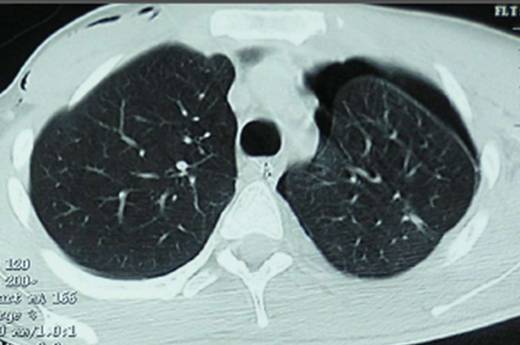

Le pneumothorax peut être spontané (son origine est alors inconnue), traumatique ou secondaire à une maladie pulmonaire.

Le pneumothorax désigne un échappement d'air du poumon qui va entre le poumon et la paroi thoracique dans la plèvre (organe qui recouvre le poumon et l'intérieur de la cavité thoracique).

Il se traduit par un décollement de la plèvre et une compression du poumon entraînant des douleurs et des difficultés à respirer.

En cas de pneumothorax, une sorte de poche d'air se forme entre le poumon et la plèvre, laquelle fait pression sur les poumons.